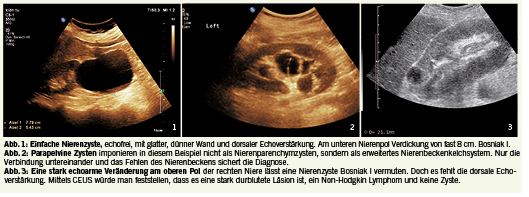

Diese Zysten sind rund, dünnwandig, ohne Septen und zeigen im Ultraschall eine dorsale Echoverstärkung, in der Kontrastuntersuchung (CEUS, CECT oder CEMR) zeigen sie keine Kontrastierung. Sie entstehen im Nierenparenchym und werden daher auch Parenchymzysten genannt (Abb. 1). Ähnlich sehen auch parapelvine Zysten aus, die ihren Ursprung im Sinus renalis haben (Abb. 2). Es kommt auch vor, dass eine einfache Bosniak I Zyste durch zystoide Formen des Non-Hodgkin Lymphoms in der Niere vorgetäuscht wird (Abb. 3). In der Regel kann man Bosniak I Zysten sicher mit einer B-Mode Sonographie diagnostizieren, nur atypische Ausnahmen machen eine CEUS-Untersuchung notwendig (z.B. Non-Hodgkin Lymphom, das im Gegensatz zu einer Zyste perfundiert ist).

Charakteristika Bosniak I Zyste:

• Wand dünn < 2 mm

• Septen keine

• Zysteninhalt echofrei

• Kontrastierung keine

• Solide Anteile keine